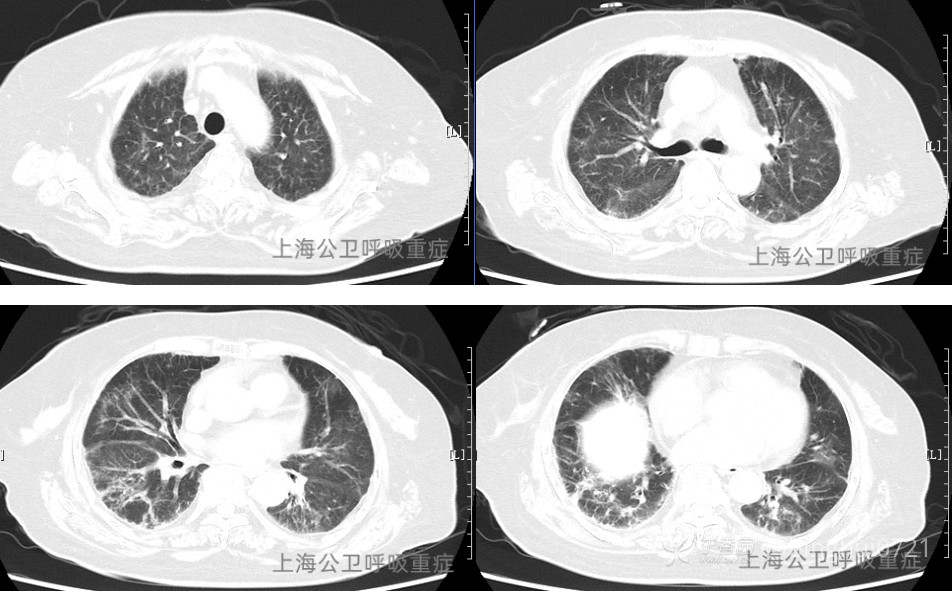

胸部CT平扫:两肺散在多发炎症,两侧少量胸腔积液,较前片继续好转。心脏增大,心包少量积液。(见图4)

图4